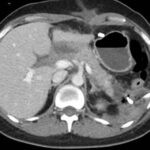

Paciente femenina de 48 años de edad que ingresa a Hospital Sanatorio Franchin por síntomas de cefalea y mareos, cuadro que se hace progresivo, presentando síncopes y posteriormente alteración del estado de conciencia. Los exámenes clínicos revelan una glucosa de 40 mg/dl, concomitante con insulina alta y péptido C elevado. Ingresa de forma programada para realización de duodeno pancreatectomía el 29 de mayo de 2021. Imágenes diagnósticas muestran estudio trifásico de tomografía de abdomen, lesión nodular en la cabeza del páncreas con ávido realce en fase arterial que en resonancia magnética se observa hiperintensa en T2, presenta restricción con la difusión y caída de la señal en el ADC. Además presenta realce tras la administración de contraste con gadolinio.

Ahora bien, como se mencionaba al principio, el estudio ecográfico es de muy baja sensibilidad y se identifique o no la lesión por este estudio, nuestro siguiente paso en el algoritmo diagnóstico de esta lesión es la tomografía. Esta es la prueba no invasiva inicial, con una sensibilidad del 63% al 83%, y detecta del 70% al 80% de los tumores. Esta debe realizarse como un estudio trifásico: fase arterial temprana a los 30 segundos, fase venosa a los 70 segundos, fase tardía de 3 a 5 minutos. La característica de estos tumores por tomografía es que se presentan como una masa sólida que tiene un ávido realce en la fase arterial, cuyo realce se mantiene y se observa más tenue en la fase venosa y en los tiempos tardíos la lesión se homogeniza.